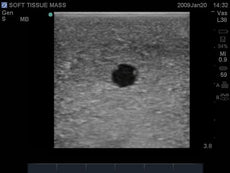

The ultrasound tissue insert offers extremely realistic sonographic imaging characteristics is designed for guiding the placement of needles and small catheters (18-21 gauge and associated catheter kits). Blue Phantom simulated human tissue is very realistic and ultra-durable; excellent for repeated training in skills associated with ultrasound guided thoracentesis procedures. Positive fluid flow offers users feedback when pleural effusions are accurately accessed. The fluid is easily refilled using a quick fill luer lock or can be connected to an I.V. reservoir for continuous fluid delivery. Users can also learn to avoid accessory structures as the spleen, diaphragm and lung.

Ultrasound imaging skills include; using ultrasound system controls, transducer positioning and movement, recognition of thoracic anatomy, lung, diaphragm, anterior spleen and pleural effusions, using ultrasound to target the appropriate fluid pockets for needle guidance, and performing an ultrasound guided thoracentesis procedure. Our self-healing tissue will allow you to repeatedly perform ultrasound guided thoracentesis procedures without giving second thought to wearing out the tissue or calculating the cost per cannulation. You can expect unmatched durability from our tissue. This ultrasound training mannequin is constructed using Blue Phantom’s patented ultra-durable tissue and is extremely realistic in ultrasound imaging characteristics and feels like real human tissue. Our self-healing tissue will withstand tremendous use and will save you money by dramatically reducing the necessity for purchasing replacement parts. Constructed using Blue Phantom simulated tissue which match the acoustic characteristics of real human tissue so when you use your ultrasound system on our training models, you experience the same quality you expect from imaging patients in a clinical environment.

The ultrasound tissue insert offers extremely realistic sonographic imaging characteristics is designed for guiding the placement of needles and small catheters (18-21 gauge and associated catheter kits). Blue Phantom simulated human tissue is very realistic and ultra-durable; excellent for repeated training in skills associated with ultrasound guided thoracentesis procedures. Positive fluid flow offers users feedback when pleural effusions are accurately accessed. The fluid is easily refilled using a quick fill luer lock or can be connected to an I.V. reservoir for continuous fluid delivery. Users can also learn to avoid accessory structures as the spleen, diaphragm and lung.

Ultrasound imaging skills include; using ultrasound system controls, transducer positioning and movement, recognition of thoracic anatomy, lung, diaphragm, anterior spleen and pleural effusions, using ultrasound to target the appropriate fluid pockets for needle guidance, and performing an ultrasound guided thoracentesis procedure. Our self-healing tissue will allow you to repeatedly perform ultrasound guided thoracentesis procedures without giving second thought to wearing out the tissue or calculating the cost per cannulation. You can expect unmatched durability from our tissue. This ultrasound training mannequin is constructed using Blue Phantom’s patented ultra-durable tissue and is extremely realistic in ultrasound imaging characteristics and feels like real human tissue. Our self-healing tissue will withstand tremendous use and will save you money by dramatically reducing the necessity for purchasing replacement parts. Constructed using Blue Phantom simulated tissue which match the acoustic characteristics of real human tissue so when you use your ultrasound system on our training models, you experience the same quality you expect from imaging patients in a clinical environment.

- Superb ultrasound imaging characteristics: extremely realistic in ultrasound imaging characteristics and feels like real human tissue

- Ultrasound tissues match the acoustic characteristics of real human tissue so when you use your ultrasound system on our training models, you experience the same quality you expect from imaging patients in a clinical environment

- Excellent imaging characteristics using any ultrasound imaging system